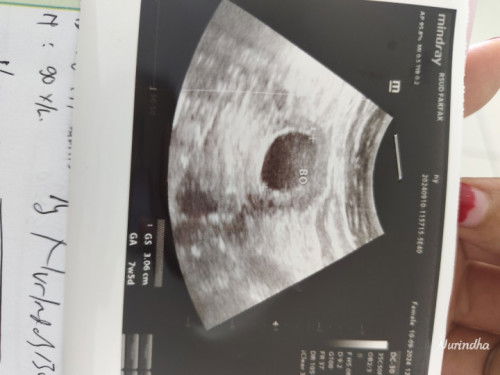

Di vonis hamil BO

Bun adakah yg sama usia 7minggu lebih tapi janin belum terlihat, disuruh balik 2 mnggu lagi.. Kata dokter kalau belum terlihat janinx lngsung di kuret🥲ada gak bunda2 pux pngalaman bgini.. Apakah masih ada harapan janin akan terlihat 2minggu kedepan..😌😌😌

selama tidak ada flek ,cba bunda USG ulang di dokter yg berbeda stlh 2 mnggu